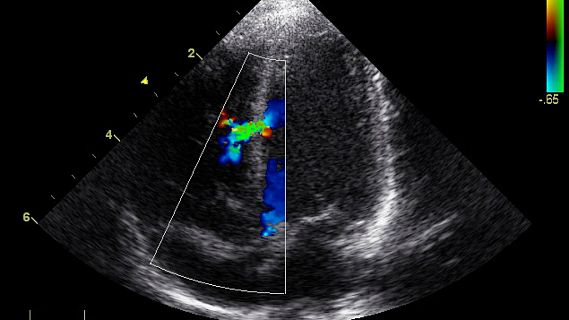

Hoy el ecocardiograma es una prueba diagnóstica fundamental para la detección de importantes problemas cardíacos y ha supuesto un antes y un después en la historia de la cardiología.